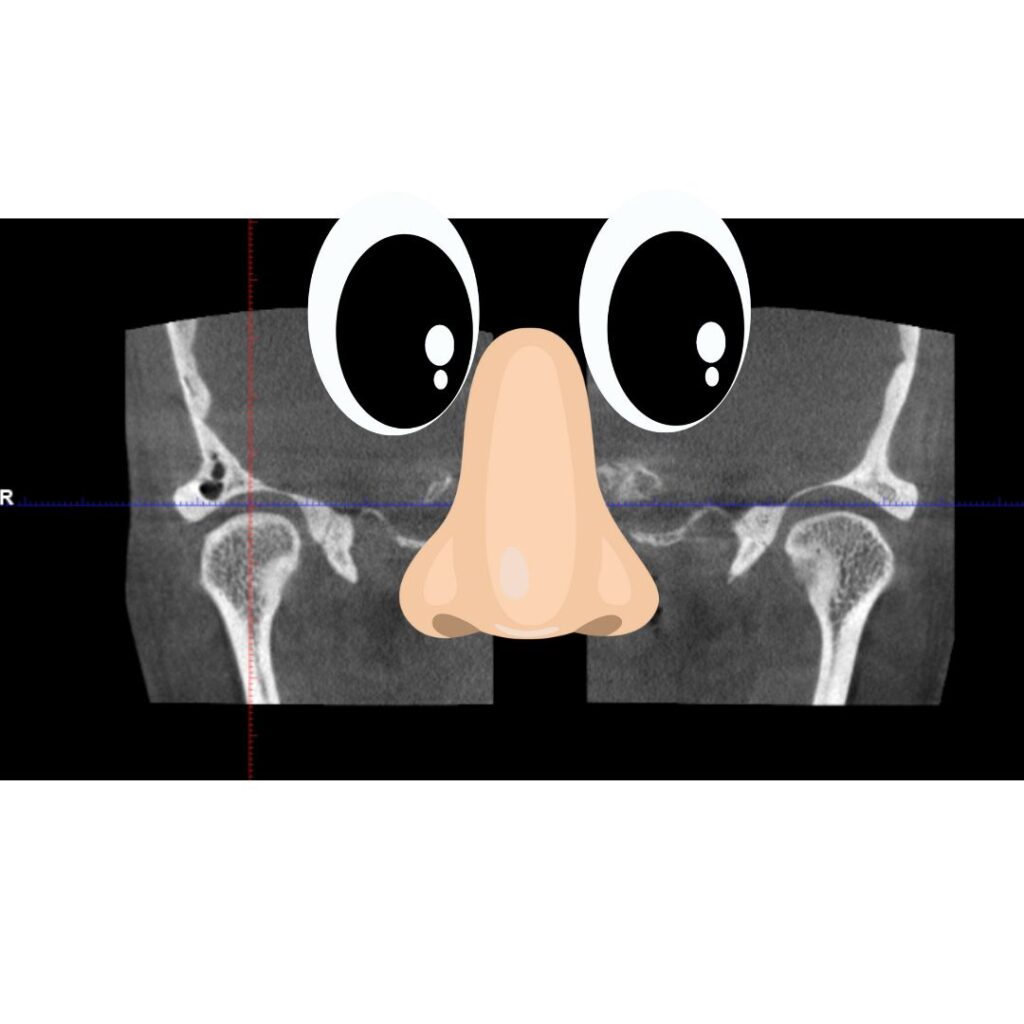

前回の噛み合わせの位置、顎の位置をマウスピースで正常化したケースです。

歯の真ん中は上下でそろいました。

その時の関節はどのように変化したか?です。↓

両方の関節の頭が均等に見えています。

ということは関節レベルで顎の歪みがとれている噛み合わせの位置が

みつかったということです。ここからこの位置で噛むように治療をしていきます。

歪みがある顎の位置と、歪みがとれた顎の位置の前後比較です。

目と鼻を入れますので上の治療前と比べてみてください。

両顎、関節がくっきりはっきりでしょ?

顎の歪みがなくなった証拠です。